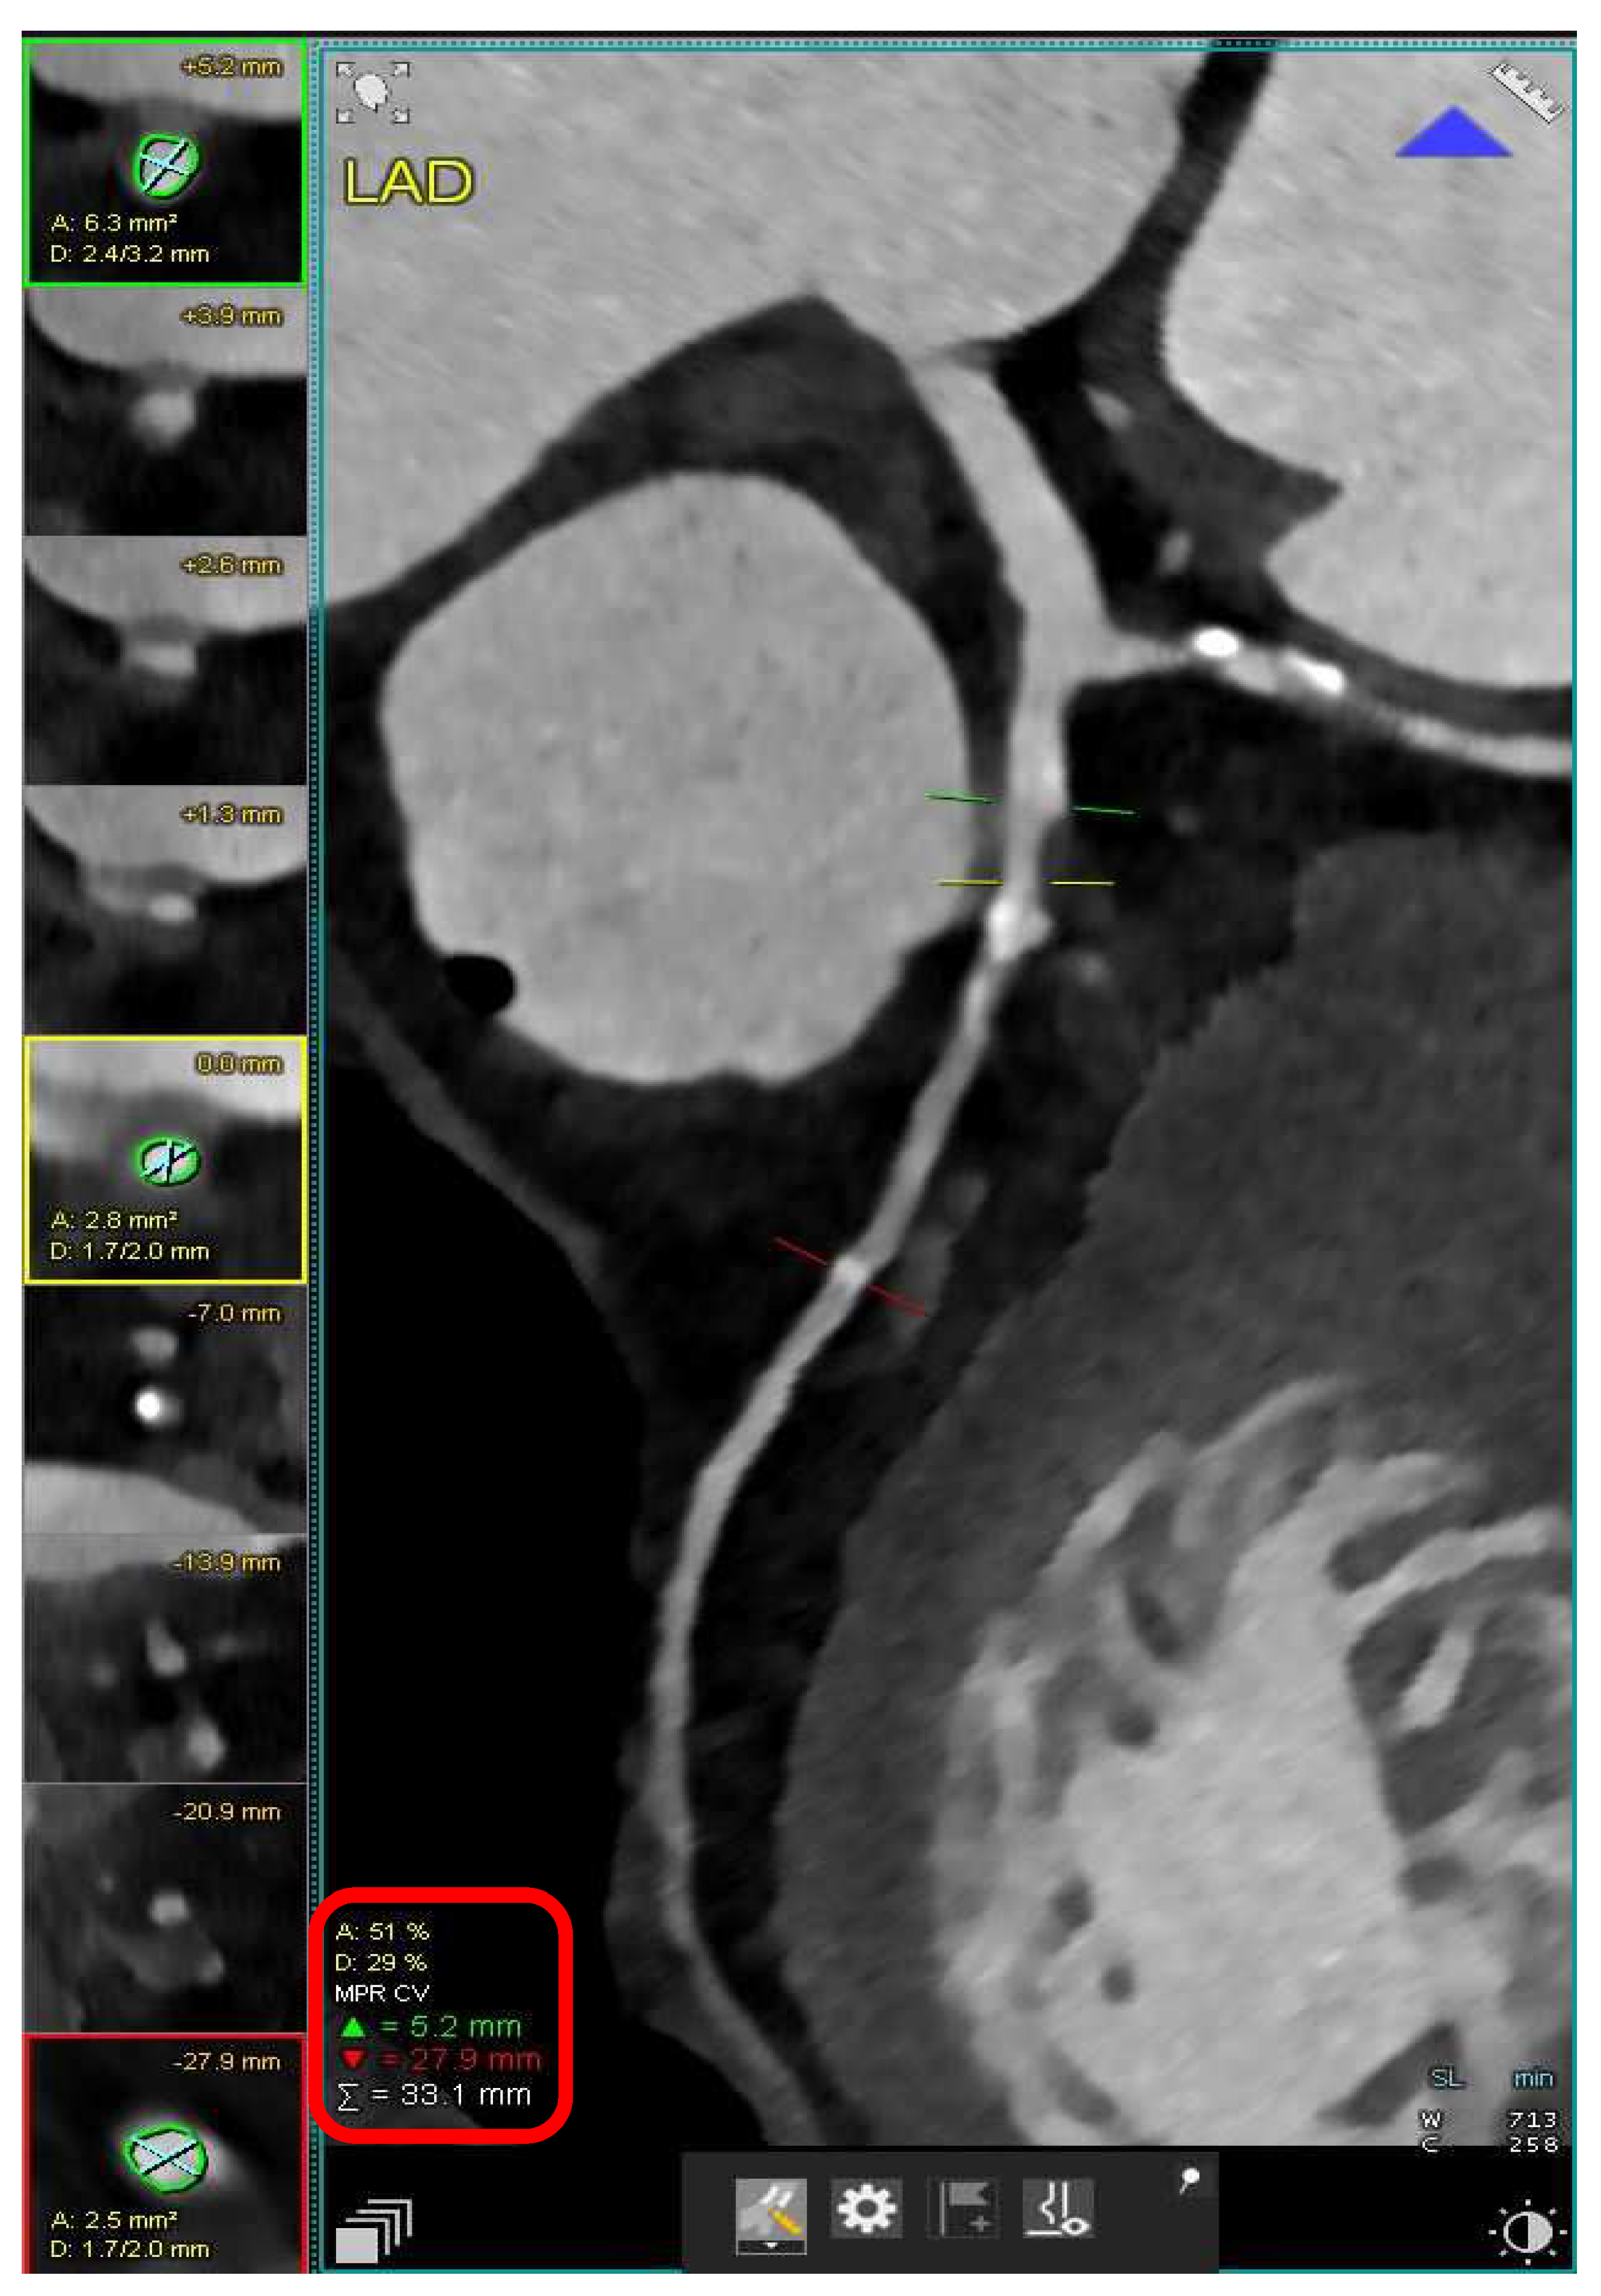

- Hulten, E.; Ahmadi, A.; Blankstein, R. CT Assessment of Myocardial Perfusion and Fractional Flow Reserve. Prog. Cardiovasc. Dis. 2015, 57, 623–631. [Google Scholar] [CrossRef] [PubMed]

- Kim, M.Y.; Yang, D.H.; Choo, K.S.; Lee, W. Beyond Coronary CT Angiography: CT Fractional Flow Reserve and Perfusion. J. Korean Soc. Radiol. 2022, 83, 3–27. [Google Scholar] [CrossRef] [PubMed]

- Coenen, A.; Rossi, A.; Lubbers, M.M.; Kurata, A.; Kono, A.K.; Chelu, R.G.; Segreto, S.; Dijkshoorn, M.L.; Wragg, A.; van Geuns, R.-J.M.; et al. Integrating CT Myocardial Perfusion and CT-FFR in the Work-Up of Coronary Artery Disease. JACC Cardiovasc. Imaging 2017, 10, 760–770. [Google Scholar] [CrossRef] [PubMed]

- Fairbairn, T.A.; Dobson, R.; Hurwitz-Koweek, L.; Matsuo, H.; Norgaard, B.L.; Rønnow Sand, N.P.; Nieman, K.; Bax, J.J.; Pontone, G.; Raff, G.; et al. Sex Differences in Coronary Computed Tomography Angiography-Derived Fractional Flow Reserve: Lessons From ADVANCE. JACC Cardiovasc. Imaging 2020, 13, 2576–2587. [Google Scholar] [CrossRef]